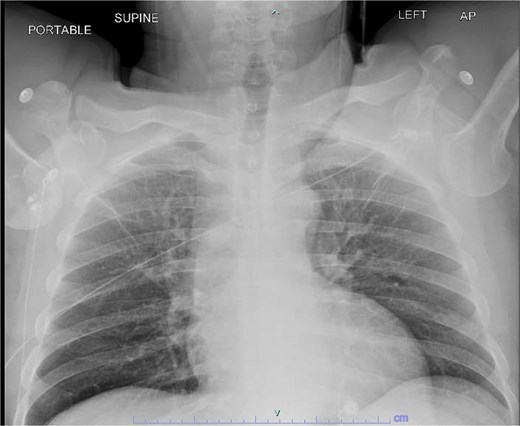

A 59-year-old right-hand–dominant male with history of prior right rotator cuff repair presented to the emergency department after a workplace injury in which four 60-lb pallets fell onto his upper back, while he was operating the steering wheel of a pallet jack. He arrived with both upper extremities locked in overhead abduction, reporting bilateral shoulder pain and hand paresthesias (Fig. 1).

Both shoulders were reduced urgently by the orthopedic team, with immediate improvement in paresthesias (Fig. 2). Post-reduction CTs were significant for bilateral chronic rotator cuff disease with superior migration of the humeral heads, right-sided supraspinatus and subscapularis atrophy, and a left nondisplaced glenoid fracture (Figs 3 and 4). He was discharged home in bilateral slings.